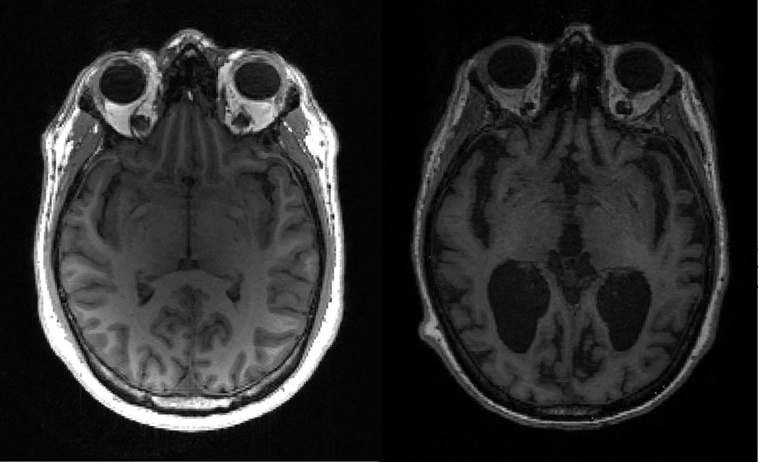

Le Leqembi fait partie d'une nouvelle génération de traitements ciblant une protéine appelée bêta-amyloïde, qui forme des plaques dans le cerveau de patients malades.